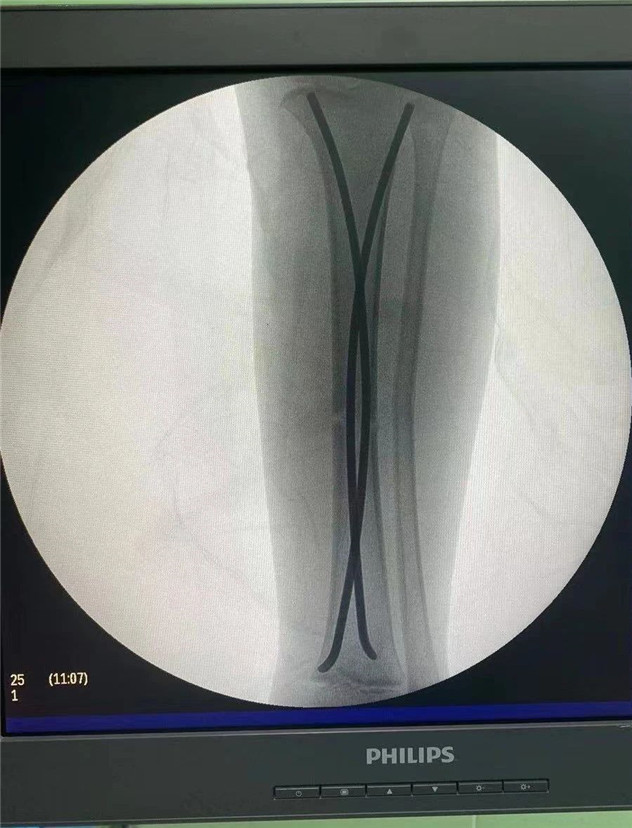

術中

2020年10月5日,在完成術前檢查后,睿睿接受了閉合復位彈性釘內(nèi)固定術,手術由羅軍主任主刀。術中只需要兩個1厘米的小切口,精準微創(chuàng),僅一個小時,手術便圓滿完成。